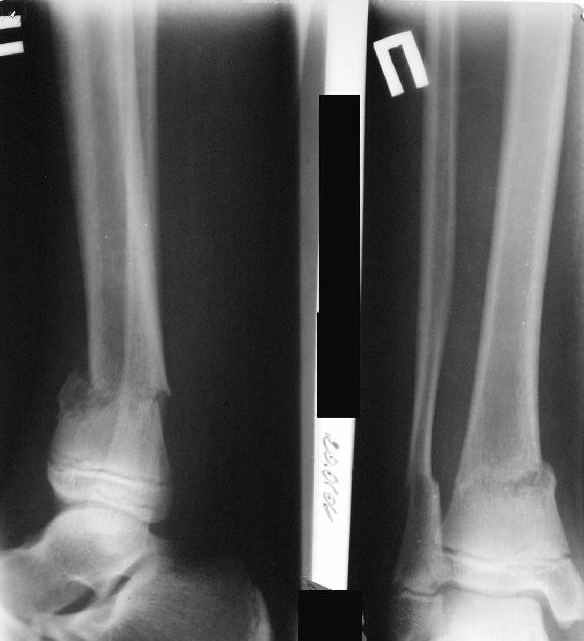

A>> Перелом костей н\3 правой голени со смещением.

AVM> Это от 13.10.04? А это близкие к первичным снимки?

Есть даже тень периостальной костной мозоли и сросшийся перелом

малоберцовой кости.

AVM> а был у больного перелом дистального метафиза большеберцовой с чисто

AVM> варусным смещением на фоне пластической деформации малоберцовой на том

AVM> же уровне и того же характера.

Это сросшийся перелом малоберцовой кости. И ложный сустав

н\3 б\берцовой кости.

Так как речь зашла непосредственно о травме, см этапные

снимки. Как все было

Первичные